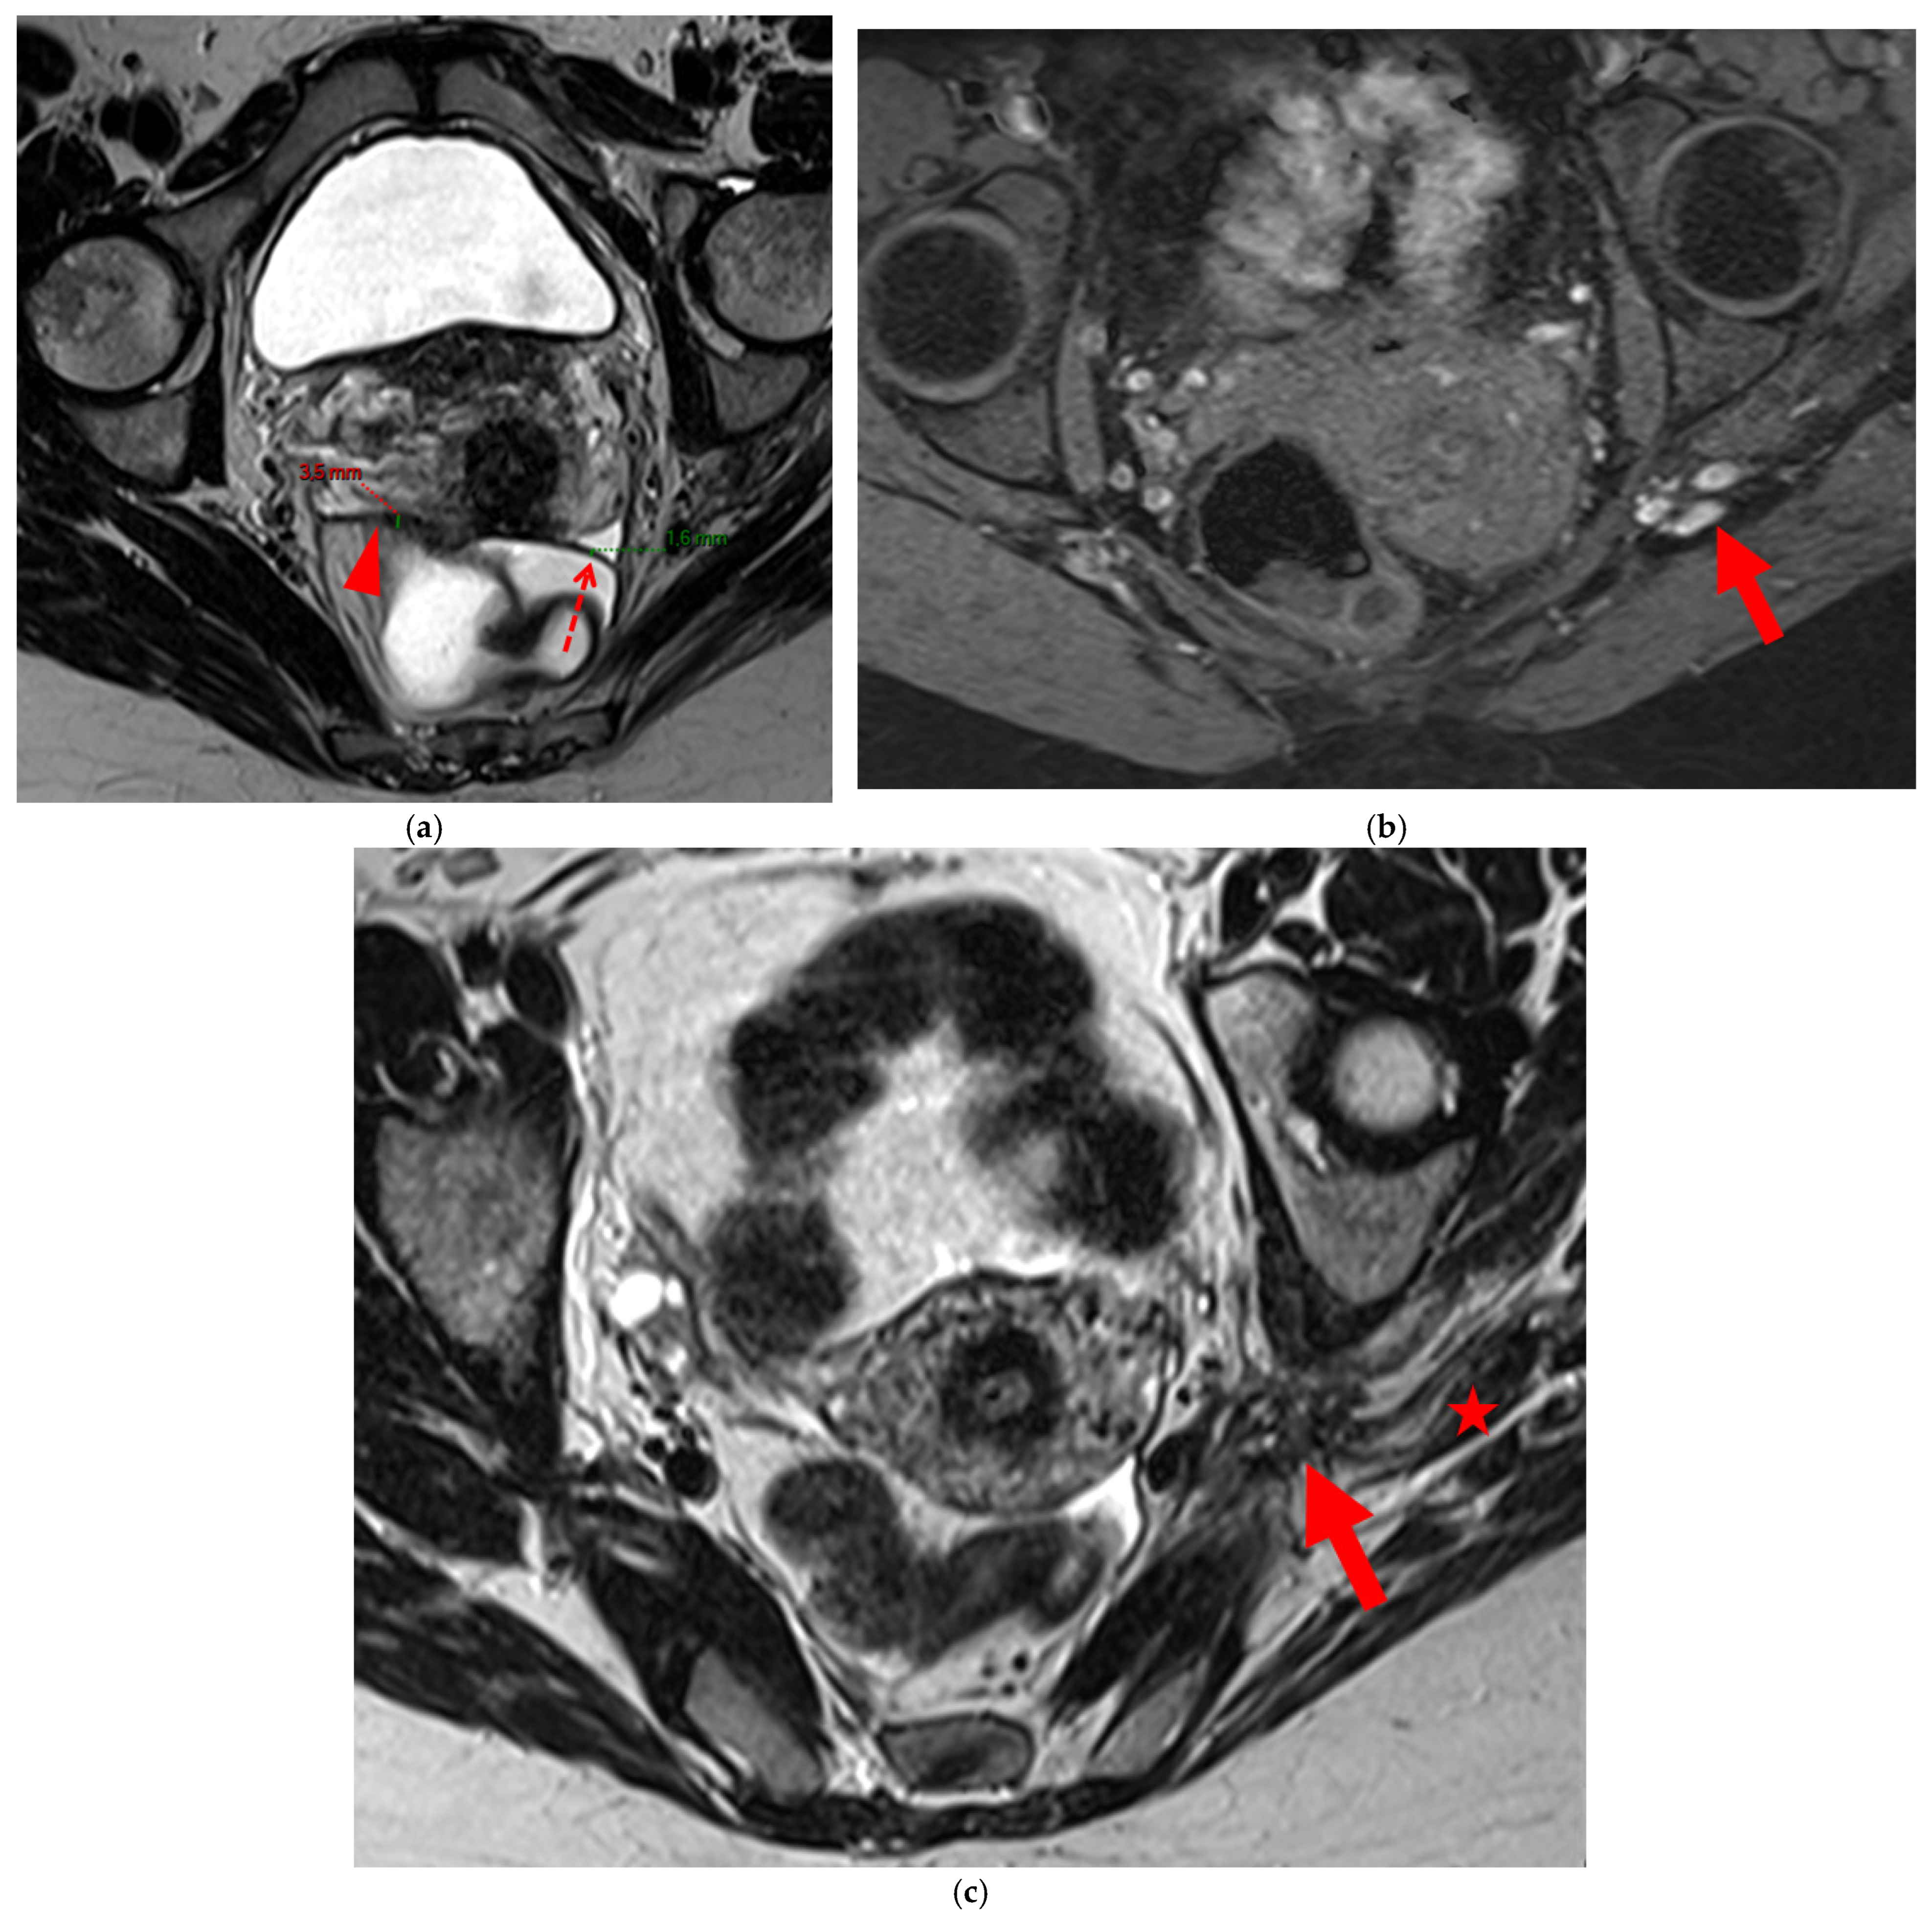

Figure 14. Pelvic MRI scan of a patient with a HTD type 6 USL. (a) Axial T2WI shows a visible but thin (1.6 mm) left USL (dashed arrow) and a thick (3.5 mm) but smooth right USL (arrowhead), initially classified as a type 2 left USL and a type 3A right USL. (b) Axial fat-suppressed T1WI reveals hyperintense hemorrhagic spots within the left sciatic nerve (arrow). (c) Axial T2WI demonstrates spiculated nodularity within the left sciatic nerve (arrow), leading to reclassification as type 6 left USL due to this so-called “visceral” nerve involvement. Note the neurogenic amyotrophy (red star) of the left piriformis and gluteal muscles, including the gluteus maximus, gluteus medius, and gluteus minimus.

A type 6 USL is associated with adjacent pelvic “visceral” involvement in a broad sense. It most commonly affects the digestive tract (Figure 8 and Figure 9), with the rectum and rectosigmoid junction wall thickening: in this case, the lesion often appears as a “medallion-shaped” protrusion into the lumen. Less frequently, the urinary tract is affected (Figure 9 and Figure 10), involving the muscular layer of the bladder or even the distal ureter at the level of the common iliac artery, with stenosis potentially leading to upstream hydronephrosis. More rarely, as USLs are also close to nearby pelvic nerve structures (Figure 11), contiguous involvement of the inferior hypogastric plexus located in the sacro-recto-genital septum (a.k.a. Delbet sagittal fascia) beneath the distal two-thirds of the USL, or exceptional involvement of the sciatic nerve adjacent to the pelvic wall, is possible (Figure 12, Figure 13 and Figure 14).